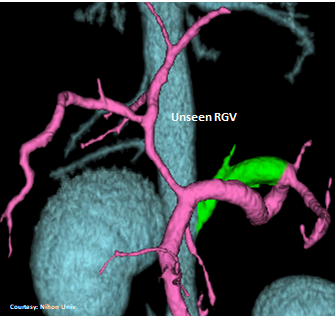

Does the RIGHT GASTRIC VEIN (RGV) contribute blood to the shunt?

WEISSE 2022

slide11